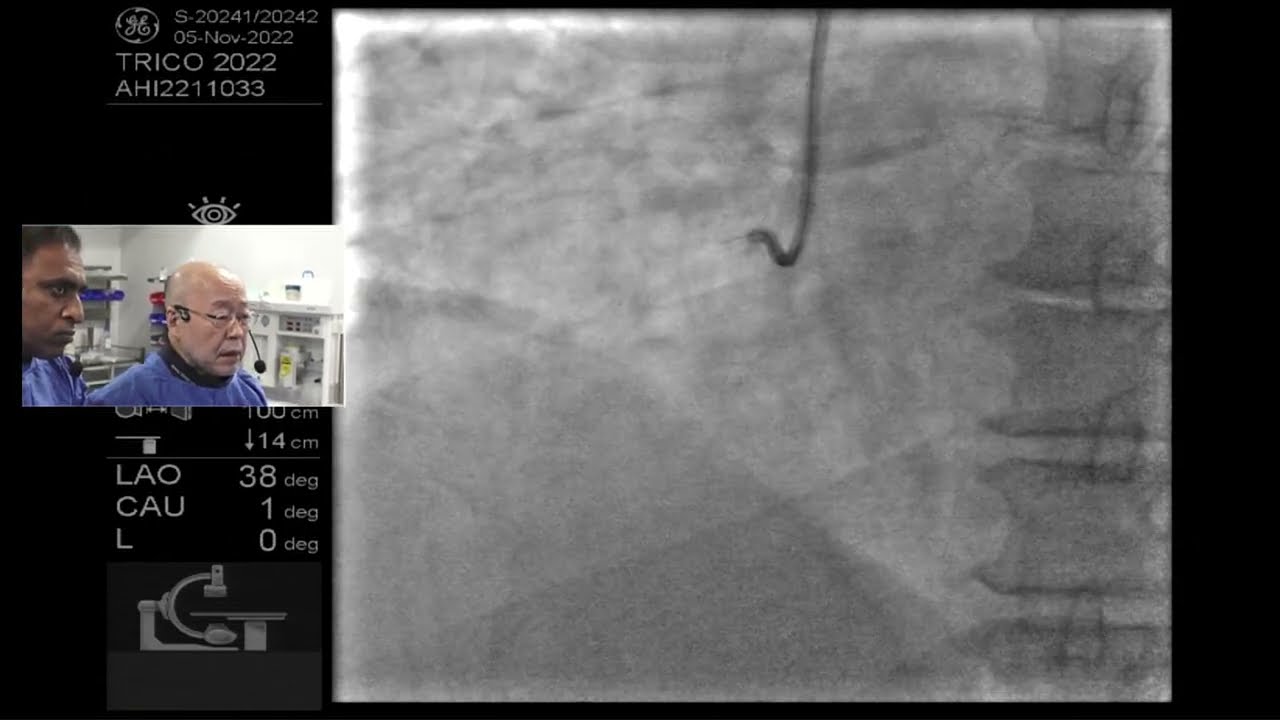

Guidewire Selection for Coronary CTO Procedures at the University Of Colorado Hospital

Описание: Interview with Kevin Rogers, M.D., director of vascular medicine at the University of Colorado Hospital. He explains what wires he uses for chronic total occlusions (CTOs). The university of Colorado is a high-volume CTO center. Read more about the Innovation at the University of Colorado Hospital Cardiology Program.

Complex CTO of RCA done by Dr. Shigeru Saito with Rajni